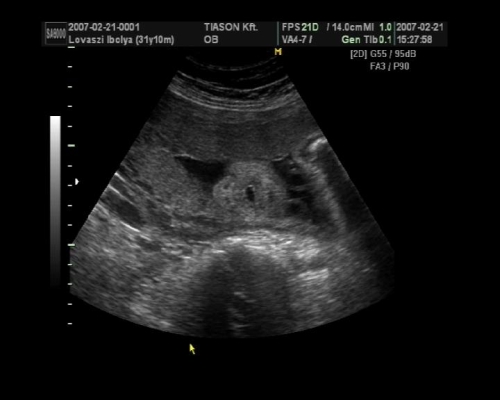

, de ami fura volt, a szívét a pocakom bal oldalán középtájban éreztem, felette pedig folyamatos rugdosást, vagy kalimpálást, De a másik oldalon ugyanott szintén... Lehet, hogy keresztben van???? De a múltkor már lent volt. Na kíváncsi vagyok kedden mit mutat az UH. Dehát azt csak lehetne látni rajtam, ha keresztben lenne...